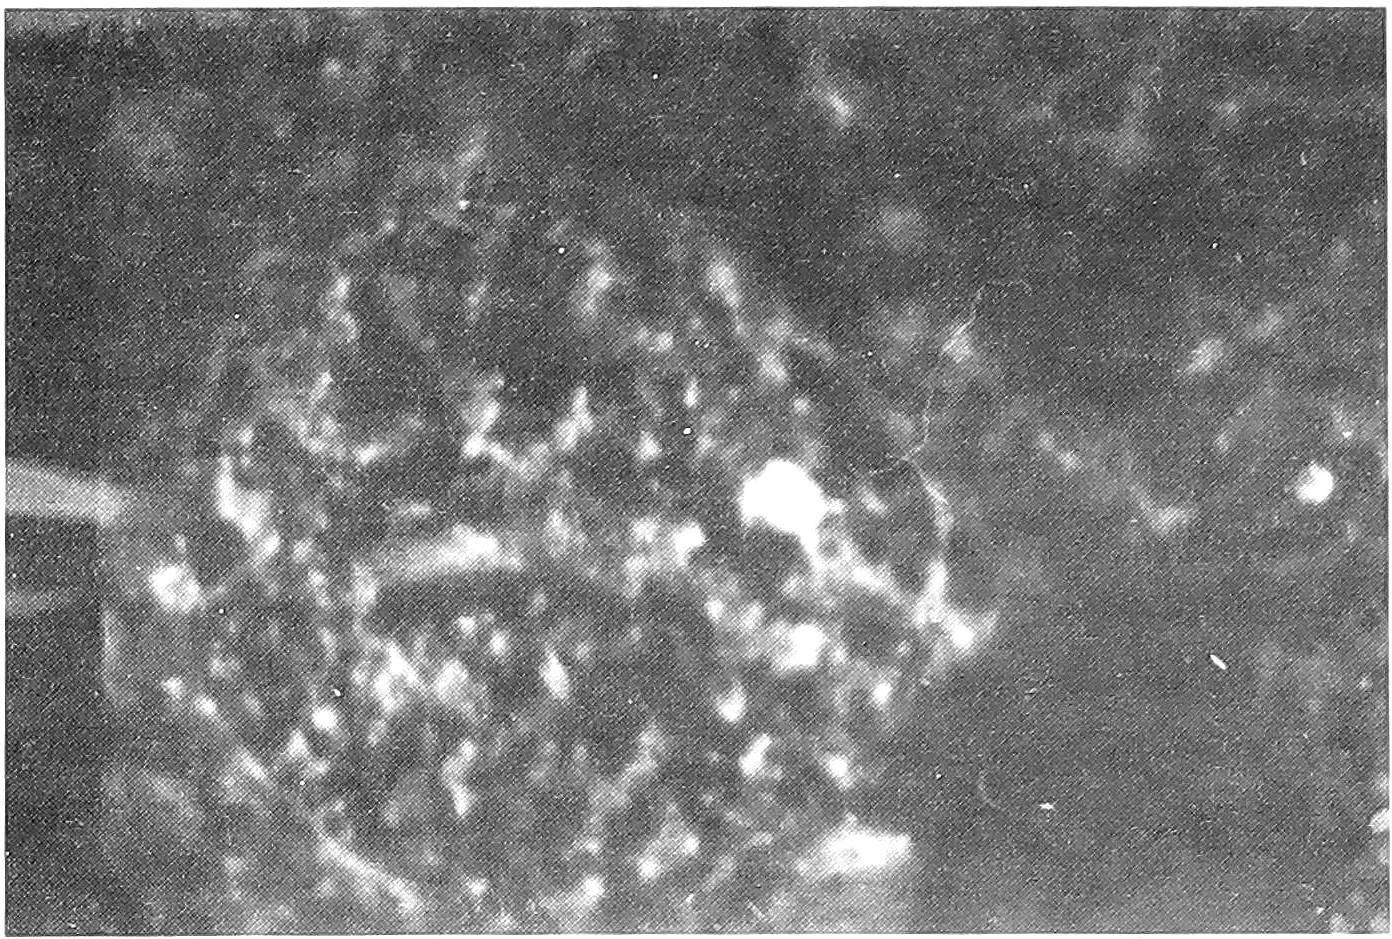

Из 29 перинатально погибших плодов и новорожденных было 7 (24,1%) с аномалиями развития. 3 из них погибли интранатально, 3 - сразу после родов и 1 - антенатально. Из 7 у трех были множественные пороки развития. У 1 - аномалия пупочного канатика, у 1 - волчья пасть и заячья губа, у 1 - врожденный порок сердца и у 1 аномалия развития почек. Все женщины, родившие детей с множественными пороками, перенесли ОРВИ до 5 нед. беременности. У всех трех в плаценте и органах плода выделен антиген гриппа A (H1N1). Мать ребенка, родившегося с волчьей пастью и заячьей губой, ОРВИ перенесла в 5 нед. и затем еще многократно при беременности. В плаценте и печени ребенка выделен антиген А (H1N1), в легких и мозге - A (H1N1) и PC. И в плаценте, и мозге ребенка с врожденным пороком сердца выделен антиген АД, а из печени АД + А (H1Nl) (pиc. 1,2, 3,4).

Рис. 1. Специфическое свечение антигена гриппа A (H2N2) в плаценте. Метод прямой иммунофлуоресценции, ув. 200.